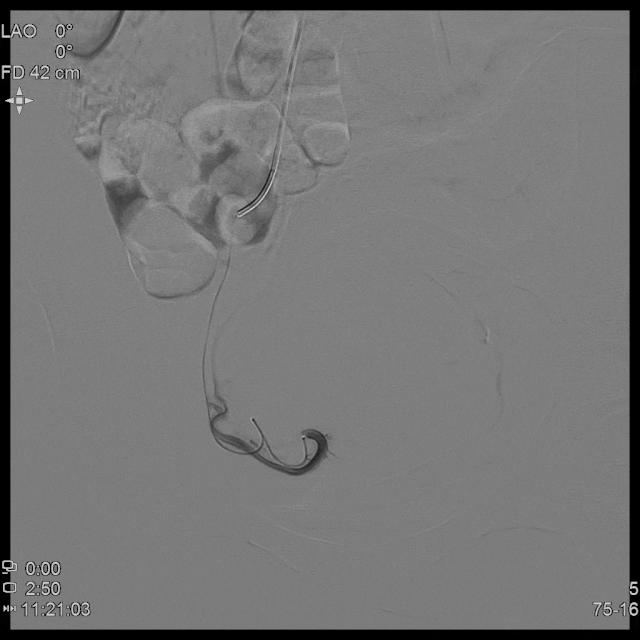

- 进一步超选插管右侧子宫动脉造影确认位置